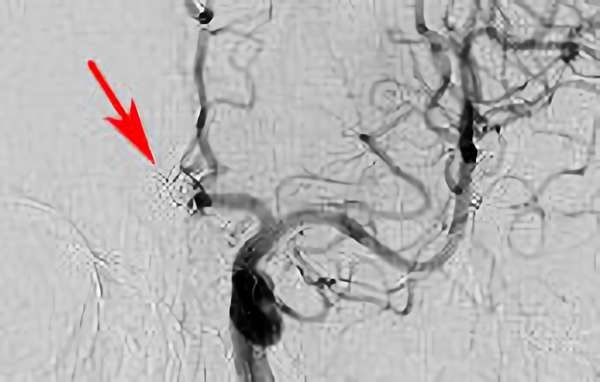

No.1630 手術前